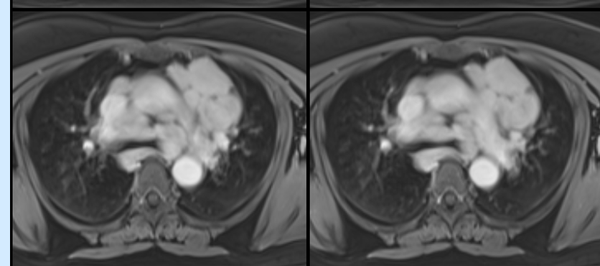

Granulomatous Cardiomyopathy

Cardiac Sarcoid